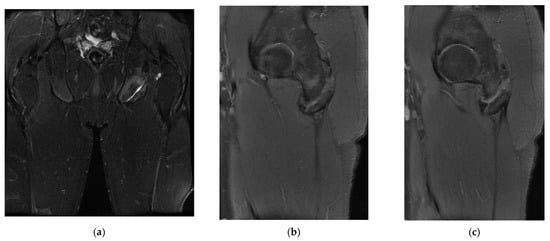

In the third case, a left winger reported experiencing sharp pain in the inner left thigh, which severely impaired both active and passive movements during sprints. The left winger, aged 32, has 14 years of experience as a first-league professional in Romania and is a national team member from an urban area, standing 189 cm tall and weighing 90 kg. MRI confirmed the diagnosis of tears and disinsertion of the short adductor tendon and I- and II-degree tears of the obturator externus, pectineus, and adductor longus muscles. STIR sequences show the disinsertion of the short adductor tendon with a gap between the tendon and pubis, with the presence of significant hyperintense alterations, which were also present in the obturator externus, pectineus, and adductor brevis muscles, representing various degrees of fiber tears associated with blood clots (Figure 8).

Figure 8.

(a) Thigh MRI: coronal stir acquisition, (b) thigh MRI: coronal stir acquisition, (c) thigh MRI: axial stir acquisition.

As the reinsertion of the adductor brevis muscle involved an unacceptable period of incapacitation, the adductor magnus, the strongest muscle in the adductor group, being unimpaired, conservative treatment was applied, the player started a physical therapy program focusing on healing first- and second-degree muscle damage, respectively, the hypertonicity and hypertrophy of the other adductor muscles, mainly of the adductor magnus, the strongest muscle in the group. He returned to play after 6 weeks.